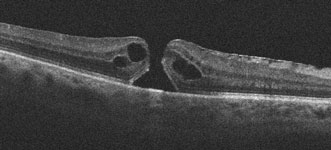

A macular hole consists of a small, round defect in the central macula, the part of the retina we use for our straight-ahead vision. The hole is thought to be caused by the vitreous pulling on the central macula, creating a central defect in the retinal tissue. It usually occurs for no obvious reason (idiopathic), although a macular hole can also be caused by trauma or retinal detachment. Macular holes are most common in women in their early 60’s and are not associated with any systemic medical problems. Approximately 10% of patients with a macular hole in one eye will eventually develop a macular hole in the other eye.

You can’t diagnose a macular hole by looking in the mirror since your eye will usually look and feel normal. The diagnosis is made with a thorough retinal examination through a dilated pupil. Early stages of macular hole formation are often difficult to diagnose, often requiring additional testing such as OCT scanning which offers a near microscopic macular image.

Vitrectomy surgery is performed in the operating room under local anesthesia. This advanced microsurgical technique allows us to restore vision by peeling and removing the vitreous from the macular surface and then filling the eye with a special gas bubble. The gas bubble helps to seal and flatten the hole postoperatively.